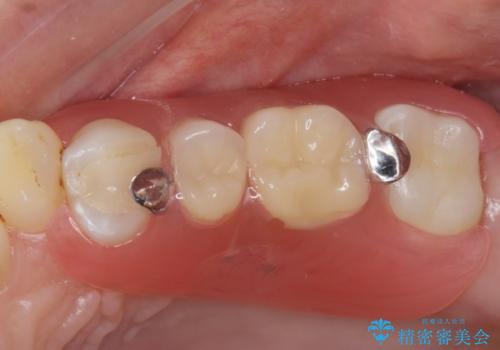

部分入れ歯のご案内をしました。なるべく銀は見えたくないとの希望により保険の入れ歯ではなく自費の入れ歯(ノンクラスプデンチャー)を作製しました。

- ノンクラスプデンチャー 16.5万円費用は治療当時の料金となります

ノンクラスプデンチャーは保険の入れ歯に比べて異物感が少なく、またメタルの部分も少ないので目立ちません。